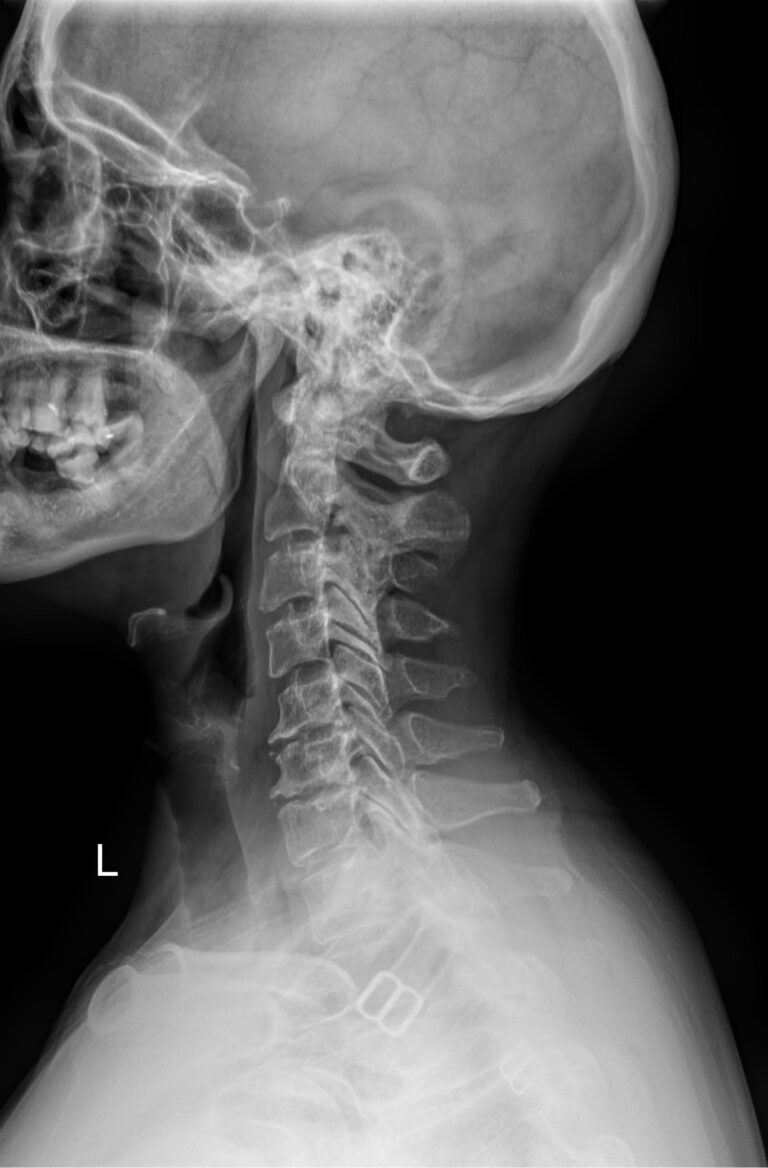

Функциональные исследования помогают выявить гипермобильность шейных позвонков или функциональный блок. Часто пробы позволяют определить начало остеохондроза, признаки которого на снимках в прямой и боковой проекции еще не заметны.

• Сохранение или сглаживание естественного лордоза в нейтральном положении, то есть на первом снимке;

• Смещение вперед или назад каждого позвонка по отношению к нижележащим при сгибании и разгибании;

• Деформацию передней стенки позвоночного канала из-за смещения позвонков;

• Сужения, расширения или отсутствие изменений межпозвоночных пространств;

• Изменения формы тел позвонков, наличие остеофитов;

• Аномалии развития.

В качестве подготовки необходимо снять все металлические украшения с шеи и головы, расстегнуть пуговицы и надеть защитную накидку. Диагностика выполняется в положении стоя или сидя, всего делается 3 снимка:

• В боковой проекции ― строго боком к детекторной пластине;

• В условиях максимального разгибания головы назад;

• В положении максимального наклона головы вперед.